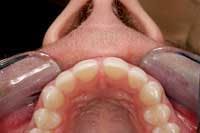

If a tooth has been missing for some time, it becomes necessary to create the same type of socket that existed in the extraction scenario. As part of the planning process for this type of case, an occlusal photograph should be taken of the proposed surgical site to determine whether or not there is enough bone thickness faciolingually to perform the procedure (Fig. 1).